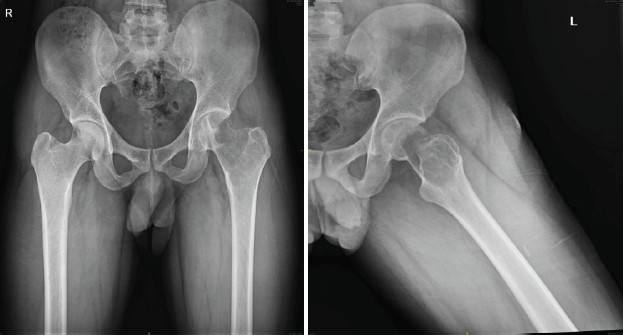

A 29-year-old man from South India presented with pain in the left hip for the past 1 year, with increased intensity for the past 5 months. Pain was dull aching, continuous without any diurnal variation. He also has difficulty walking for the past 5 months. On examination, there was tenderness around the left trochanteric region and around the joint line. His movements of the hips were restricted and extremely painful. He was primarily wheelchair-bound with limited mobility. His X-ray and computed tomography (CT) scan showed an eccentric expansile lytic lesion measuring approximately 7.7 × 5.7 × 3.2 cm in the proximal left femur involving the superolateral portion of the femoral head, neck of femur, greater trochanter and intertrochanteric region (H1 and H2 area and minimal involvement of H3 area as per the International Society of Limb Salvage) with no matrix mineralization [Fig. 1 and 2].

Figure 1: X-ray pelvis shows large lytic cavity in the femoral head, neck, and trochanteric area of the left proximal femur. These are pre-operative X-rays taken before the surgical procedure, at the time of presentation.